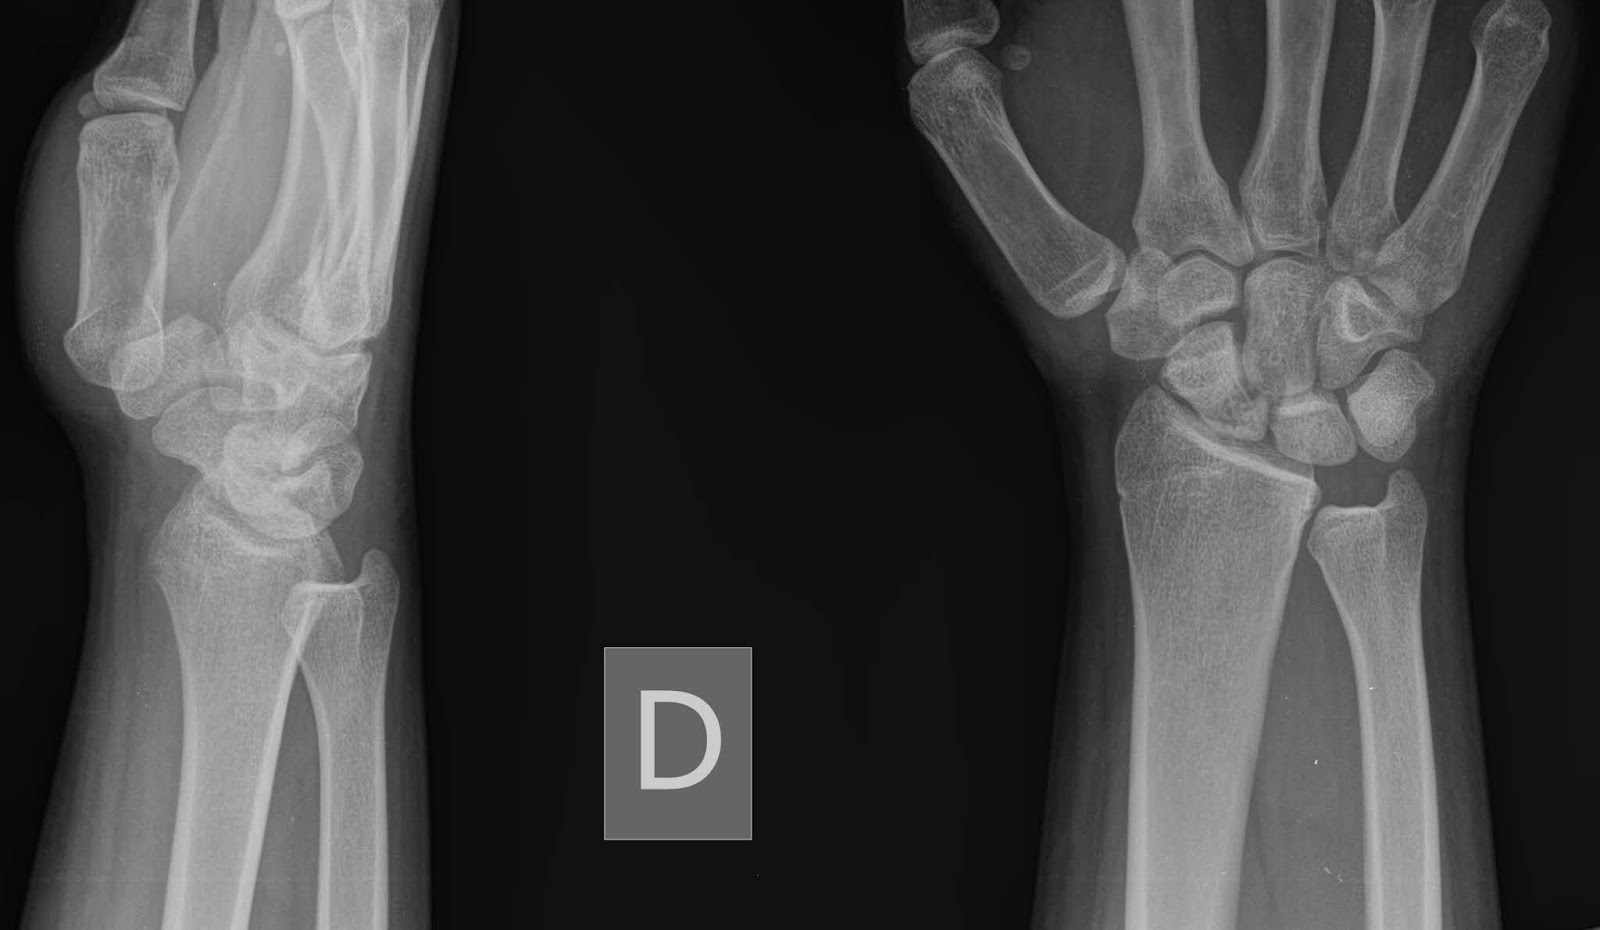

Cirugía de Mano y Traumatología: Pruebas Radiológicas para la fractura

Source: manoytrauma.blogspot.com